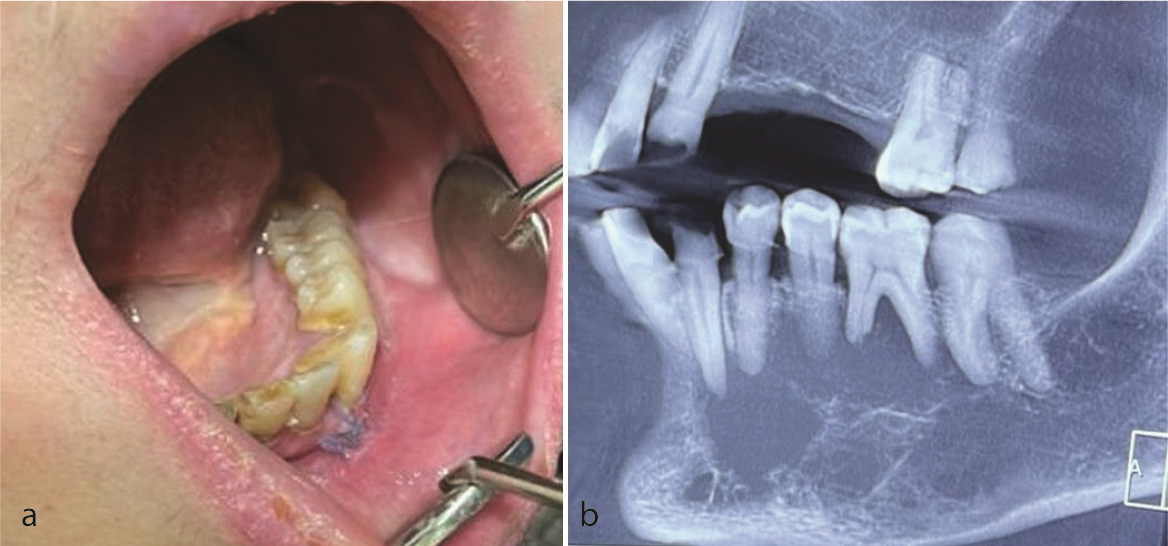

A 57-year-old woman with a chief complaint of left lo-were face swelling was referred to a private dental clinic (Qom, Iran) in October 2023. The intraoral examination revealed mild buccal and lingual expansion from the left lateral incisor extending to the second molar without any mucosal erosion or ulcer. There was no cervical lymphadenopathy (Figure 1a-b). Cone beam computed tomography (CBCT) showed a multilocular radiolucency from tooth 32 to 37 with right angle septa and cortical destruction. The extension of the lesion was more than its expansion (Figure 2). She had a history of right breast cancer in 2017 with a microscopic diagnosis of invasive ductal carcinoma, solid type, stage IIIc. She had undergone a wide surgical excision and chemo-radiotherapy. She took bisphosphonates and was under follow-up. Due to past medical history and radiographic features, a provisional diagnosis of odontogenic myxoma, metastatic cancer, and leukemia/lymphoma was made, and an incisional biopsy was performed under local anesthesia. Histopathologic examination showed a malignant neoplasm composed of sheets of small round cells with hyperchromatic nuclei and mitosis. Considering the medical history and microscopic features, an overall diagnosis of a small round cell tumor was rendered, and immunohistochemical (IHC) staining for cytokeratin (CK), leukocyte common antigen (LCA), CD-99, GATA3, estrogen (ER), progesterone (PR), and HER-2 was recommended. IHC was only positive for GATA3 and CK (Figure 3b, Figure 4a). Findings were consistent with metastatic carcinoma of breast origin. In whole-body scans and CT with and without contrast, no focus of involvement was seen except for the left mandibular area. Tumor markers such as CA15-3 (40.2u/ mL) were higher than the normal range (up to 31.3), but CEA (1.05ng/mL) and CA125 (12.2u/mL) were in the standard limits. Due to bone (mandible) metastasis, the patient was placed in stage IV. She was referred to an oncologist to complete the treatment. She has undergone two courses of chemotherapy and one course of radiotherapy, and after 13 months (November, 2024), the general condition of the patient was acceptable.

Figure 1.a: Photograph shows mild buco-lingual expansion of left mandible, b: Cone beam computed tomography (CBCT) displays a large lytic radiolucent lesion with right-angle septa